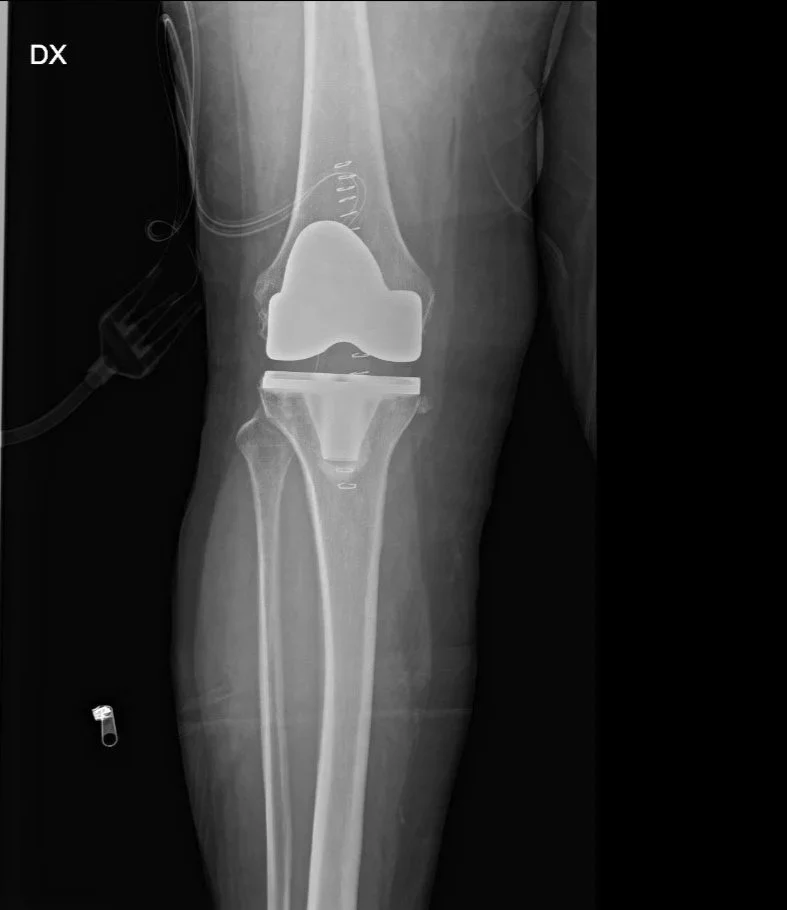

Radiografia di un ginocchio con protesi totale, utilizzata dal Dott. Fabrizio Bertelle per spiegare come mantenere nel tempo la funzionalità di un ginocchio protesico.

Protesi al ginocchio: come farla durare e funzionare al meglio per anni

La protesi al ginocchio è una soluzione potente per liberarti dal dolore cronico, recuperare mobilità e tornare a vivere senza limiti. Ma il risultato migliore, quello che dura nel tempo, non dipende solo dall’intervento: è il percorso post‑operatorio, la cura quotidiana e alcune attenzioni che fanno la differenza. Ecco come avere un ginocchio protesico performante nel lungo periodo: 7 segreti fondamentali, supportati da evidenze mediche, che ogni paziente dovrebbe conoscere.